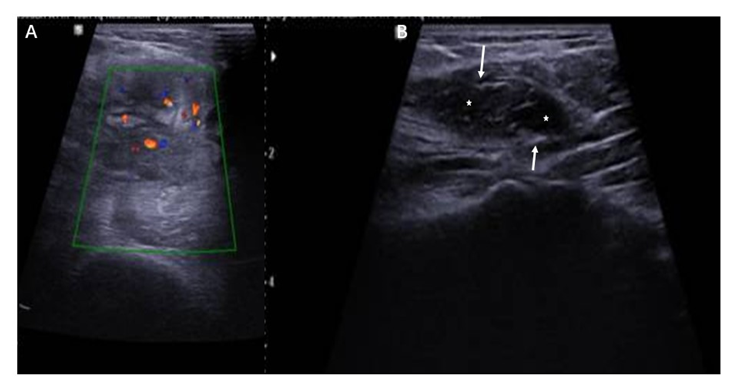

Ultrasonography is the best investigation modality in differentiating between cystic and solid lesions, and for early diagnosis of heterotopic bone formation. Ultrasonography in our case demonstrated a heterogeneous solid mass and some internal blood flow on the Doppler examination. It was noticed the hyperechoic rim surrounded by a hypoechoic rim and the central area that is hypoechoic as well (Figure 2). The calcified lesion was located over distal humerus just above the olecranon fossa on AP radiograph. The calcifications typically become more peripherally oriented and coarse in appearance with a calcified peripheral rim with a lucent center, the calcifications appear as amorphous and flocculent simulating osteoid matrix in brachial muscles (Figure 3).

Figure 2: Ultrasonography demonstrates a heterogeneous mass demonstrating some internal blood flow on the Doppler examination (red dots in A). Note the hyperechoic rim (arrows) surrounded by a hypoechoic rim and the central area that is hypoechoic as well (stars).